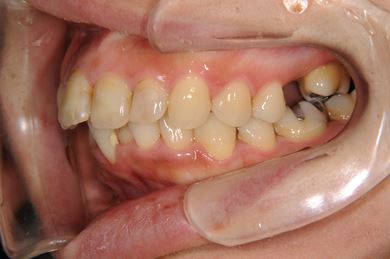

セラミックの症例写真 SHINBI

インプラント矯正治療+セラミック治療

| 性別/年齢 | 女性 / 35歳 | ||||||||||||||||||||||||||||||||

| 主訴 | 歯並び(乱ぐい歯、出っ歯)と歯の色が気になる。 | ||||||||||||||||||||||||||||||||

| 治療方針 | 左上の第一大臼歯がすでに抜歯され欠損の状態で来院されました。デンタルインプラント、あるいはブリッジで補綴するよりも、上あごが突出していること、乱杭歯があることより、矯正治療を第一選択としました。上下第一小臼歯を4本抜歯してその隙間を利用し、治療していきました。抜歯スペースをすべて効率的に利用したいため、上顎左右、下顎左側1本の計3本のインプラントアンカーを使用します。左上は第二大臼歯、智歯を利用しています。今後保定装置の針金は一生装着予定です。上顎の中切歯は左右とも人工的にかぶせものをしています。初診の歯牙変色がなくなり、審美的にもとてもよくなりました。 | ||||||||||||||||||||||||||||||||

| 治療内容 | インプラント矯正(唇側矯正ホワイト、審美ワイヤー、左右上顎第一小臼歯抜歯、上顎インプラントアンカー) | ||||||||||||||||||||||||||||||||

| 治療期間 | 1年9ヶ月 |